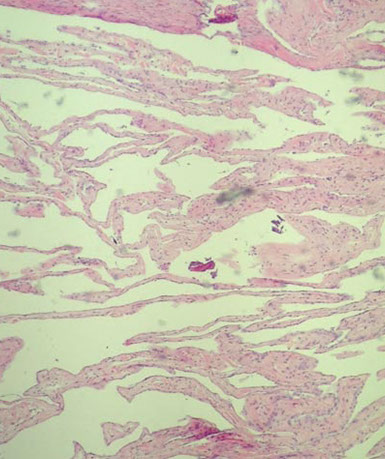

Desmoplastic infantile ganglioglioma/astrocytoma

Rare tumor that looks like the name implies

Seen in kiddos <2 yo c variable imaging findings; usually very large

Micro: atypical mixed glial and neuronal tumor c prominent desmoplasia which gets highlighted with reticulin

- invade subarachnoid space (similar to JPA, PCA, GG)

Tx: Resection

Pc: good (if young age and small tumor size)